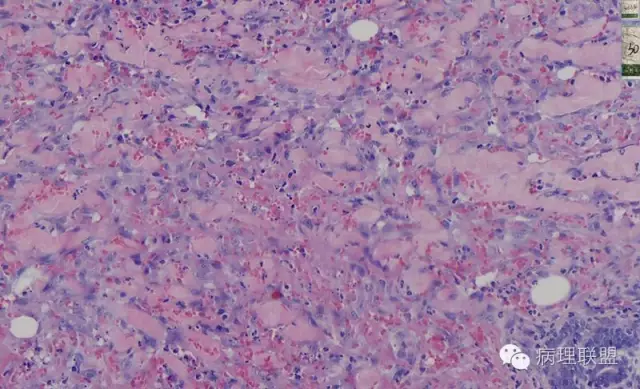

而复合性血管内皮瘤则是由良性、中间性和恶性的成份组成,也是浸润性生长,常常侵犯皮下脂肪组织,此例细胞形态由梭形细胞、卵圆形细胞及上皮样细胞组成,形态可见良性区域、中间性区域及高分化血管肉瘤或上皮样血管肉瘤区域,因此,似乎复合性血管内皮瘤更妥。此类肿瘤可以发生于婴幼儿。当然与Kaposi型血管内皮瘤一样,同属中间性血管瘤,只是后者,若肿瘤体积大,可出现Kasabach-Merritt综合征。

个人觉得应该是皮下纤维素渗出导致的内皮细胞旺炽性增生,局部呈内皮细胞乳头状增生,不认为是迷路样吻合;可能是婴幼儿血管瘤破裂诱发,也可能是血管畸形诱发。

注意活跃增生的内皮细胞总是与纤维素关系密切,并非穿插浸润的真皮胶原束。

混合型血管内皮瘤虽是混合各种形态,但是其主要成份一定是内皮瘤成份,上皮样血管内皮瘤或网状血管内皮瘤成份,其它血管肉瘤,血管瘤次要。@广医二院_病理科_梅开勇 仔细看了,好像是胶原。